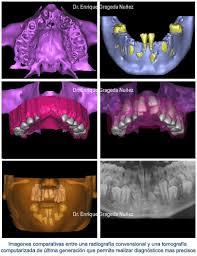

1. La infromática ha ayudado a la cirugía, con las técnicas de fabricación rápida de prototipos industriales para desarrollar modelos tridimensionales a partir de las imágenes obtenidas mediante escáneres ópticos y tomografía computarizada

2. Estos programas permiten crear guías quirúrgicas, pilares, coronas y una serie de estructuras quirúrgicas y protésicas virtuales para la planificación de un caso, realizar cirugías en modelos anatómicos fidedignos, colocar implantes, componentes protésicos y transferir después toda esta información virtual al paciente durante la cirugía.

1. La integración de las nuevas tecnologías digitales a la odontología es ya una realidad. El implantólogo debe familiarizarse con el uso de los escáneres intra y extraorales y con los programas de planificación quirúrgica guiada. Igualmente, debe tener acceso a programas de diseño por computadora y a máquinas de impresión y fresado en tres dimensiones, ya sea en su clínica o en un laboratorio que disponga de esta tecnología.